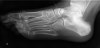

X-ray : Lover’s fracture

X-ray : Calcaneal tuberosity avulsion fracture